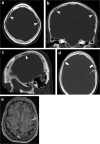

Calvarial lesions are often asymptomatic and are usually discovered incidentally during computed tomography or magnetic resonance imaging of the brain. Calvarial lesions can be benign or malignant. Although the majority of skull lesions are benign, it is important to be familiar with their imaging characteristics and to recognise those with malignant features where more aggressive management is needed. Clinical information such as the age of the patient, as well as the patient's history is fundamental in making the correct diagnosis. In this article, we will review the imaging features of both common and uncommon calvarial lesions, as well as mimics of these lesions found in clinical practice. TEACHING POINTS: • Skull lesions are usually discovered incidentally; they can be benign or malignant. • Metastases are the most frequent cause of skull lesions. • Metastatic lesions are most commonly due to breast cancer in adults and neuroblastoma in children. • Multiple myeloma presents as the classic "punched out" lytic lesions on radiographs. • Eosinophilic granuloma is an osteolytic lesion with bevelled edges.